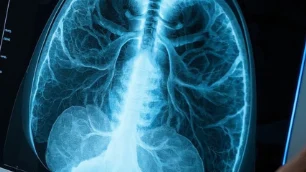

肺结节是胸部影像学检查中常见的发现,通常指的是直径小于3厘米的肺部肿块。这些结节可能是良性或恶性病变,且在影像学上表现各异。根据统计数据,肺结节在CT检查中发现的概率可高达20%至30%。随着胸部影像学技术的进步,越来越多的肺结节被发现,但并非所有的结节都有临床意义。

磨玻璃结节(Ground-glass opacity,GGO)是一种特殊类型的肺结节,其影像学特征为肺组织局部模糊增亮,边界与周围正常肺组织不清晰。这种模糊的影像特征提示可能存在病理变化,常见于多种肺部疾病,包括炎症、感染、良性病变以及早期肺癌等。

在影像学检查中,磨玻璃结节的大小、形状和边缘特征是评估其性质的重要依据。通常情况下,直径小于1厘米的磨玻璃结节更可能是良性的,而较大或边缘不规则的结节则可能提示恶性病变。在患者的案例中,CT检查显示两肺多发磨玻璃结节,最大直径为0.8厘米,这一特征在影像学上通常应引起重视。